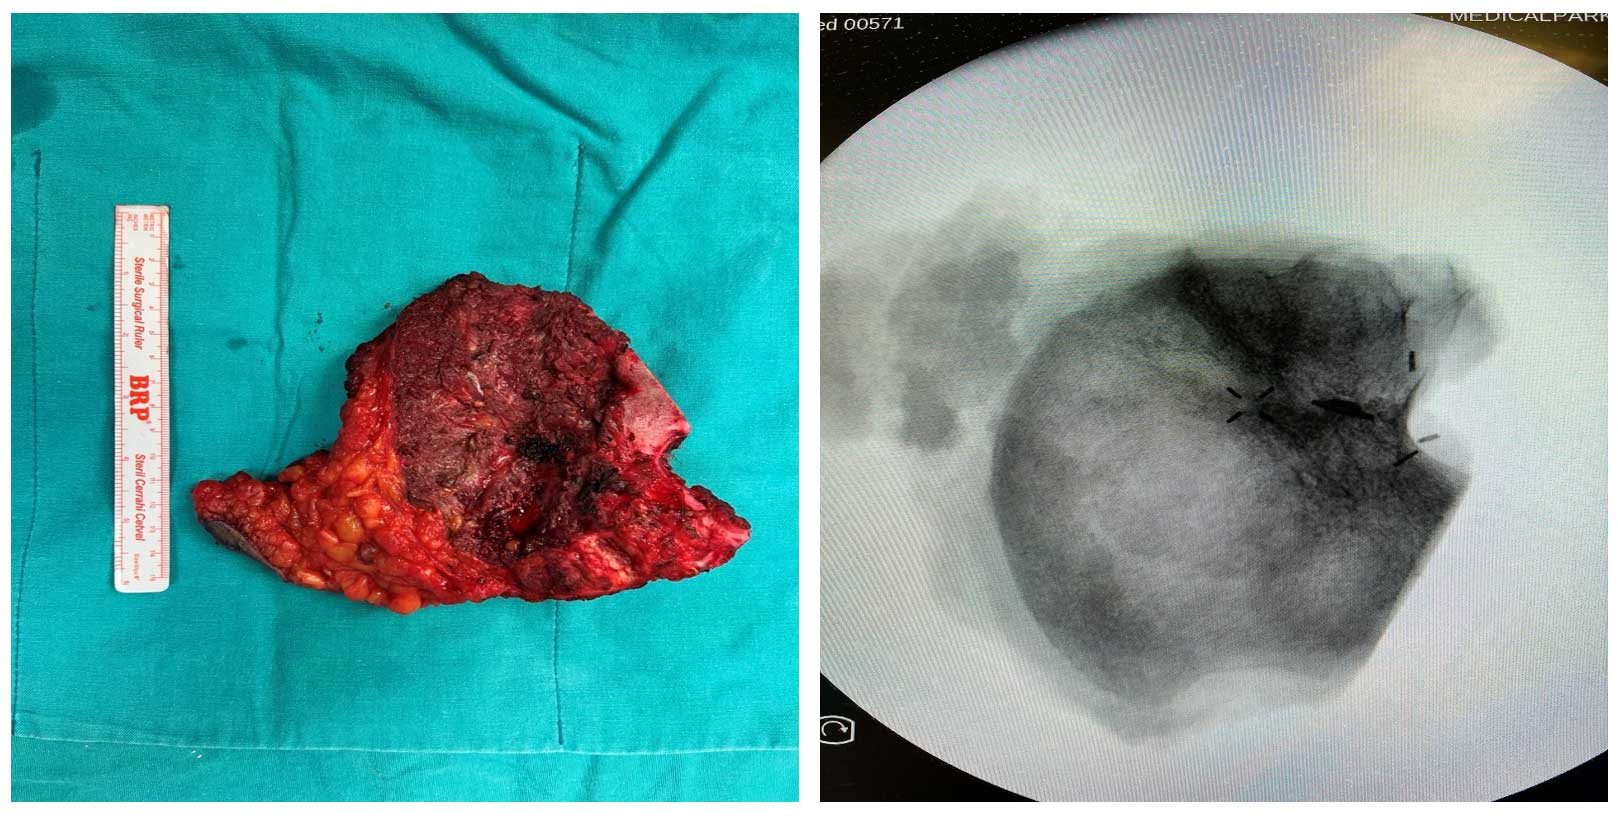

Ameliyat Esnası: Rezeksiyon dokusunun klinik ve skopi görüntüsü.